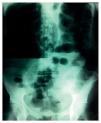

La placa simple de abdomen muestra ciego con distensión importante, nivel hidroaéreo (figura 1), sin dilatación de asas de delgado, y presencia de gas intraluminal en la ampolla rectal (figura 2). La ultrasonografía reporta peristalsis aumentada, abundante material aéreo, líquido y de residuos en marco colónico.

Figura 1 Placa simple de abdomen con dilatación en ciego y nivel hidroaéreo.

Figura 2 Ausencia de dilatación de delgado y gas.